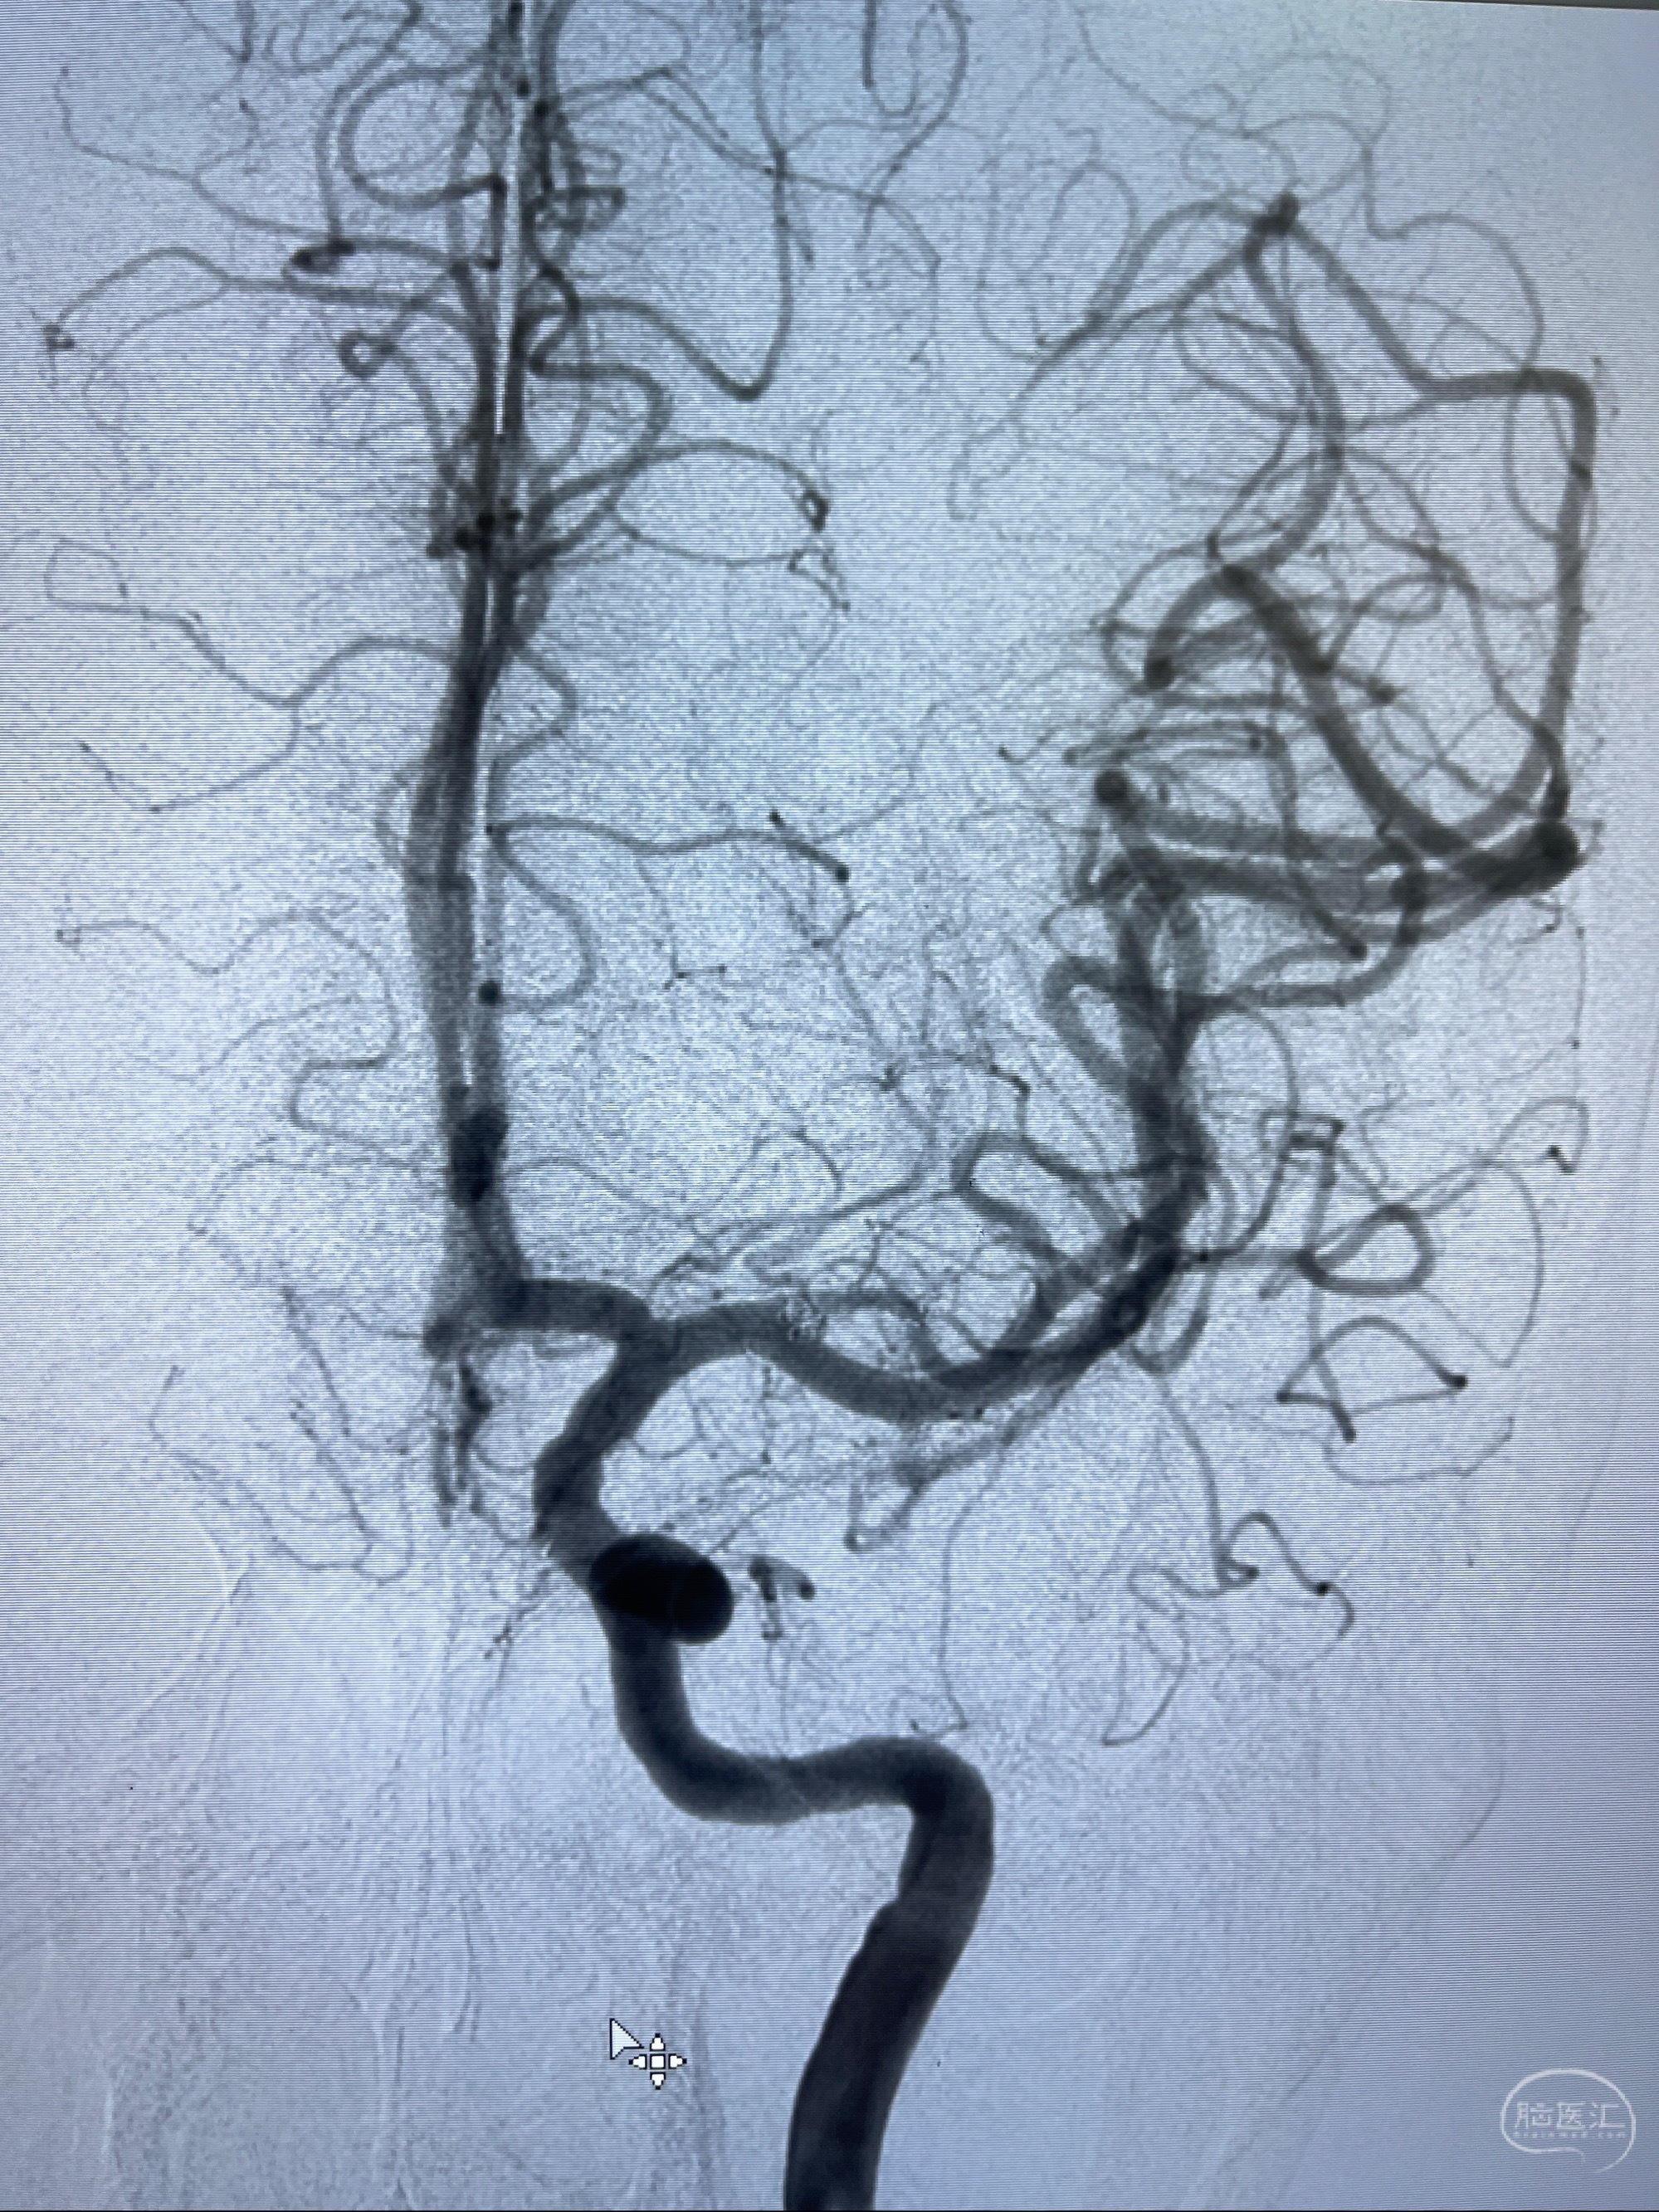

2023-08-14DSA:

左侧大脑中动脉动脉瘤,约2.6-2.8-3.4-2mm大小(瘤颈部、瘤体部、瘤高)